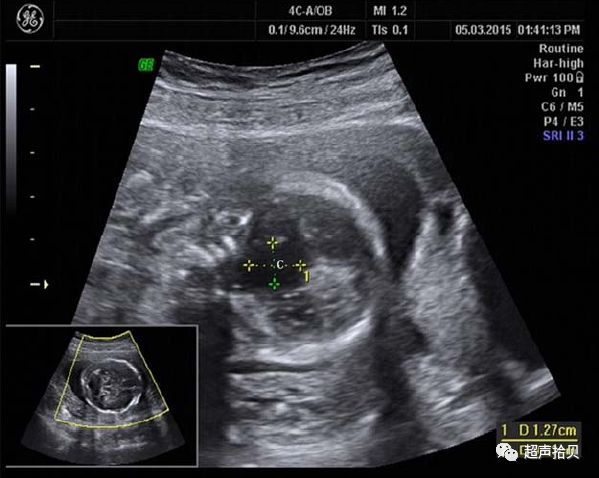

图1A,妊娠24周后胎儿的矢状面,中线囊肿直径25毫米。 B,胎儿的横断平面脑室扩大,中线囊肿。

一周后,进行第二次扫描以评估进展性结果。 囊状结构和侧脑室分别扩大到28×25毫米和13毫米大小。 矢状位图显示脑干向后位移,阻塞脑室循环(图2,A和B)。 胼胝体正常发育,血流正常,无颅内压增高(图2C)。 三维超声显示孤立的圆形囊状结构(图3)。 使用产前超声检查结果进行胎儿MRI并确认鞍上位置(图4)。 怀疑是蛛网膜囊肿,囊肿和蛛网膜下腔之间可能存在解剖联系的球阀机制被认为是囊肿扩大的原因;

图2:A妊娠25周后胎儿的矢状面。 B,囊肿和侧脑室在1周内增大至28×25和13mm。 C,矢状彩色多普勒图像显示胼胝体前动脉血流;